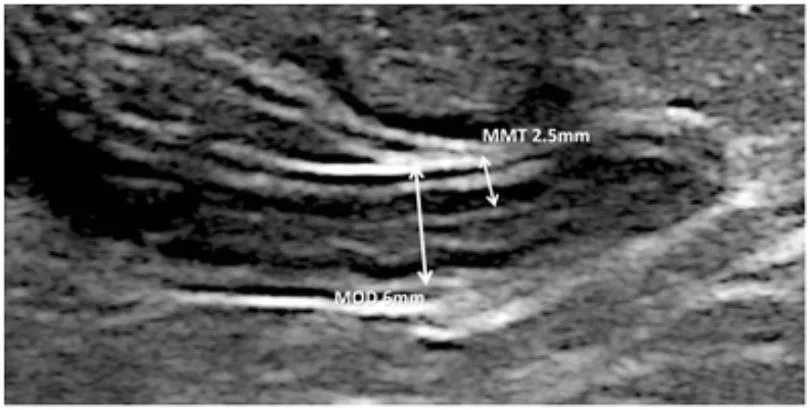

Maximal outer diameter : Maximal mural thickness

Muscularis layer에서부터 반대편 muscularis layer까지 잰다

Threshold : 6mm (민감도는 높으나, 특이도는 낮다)